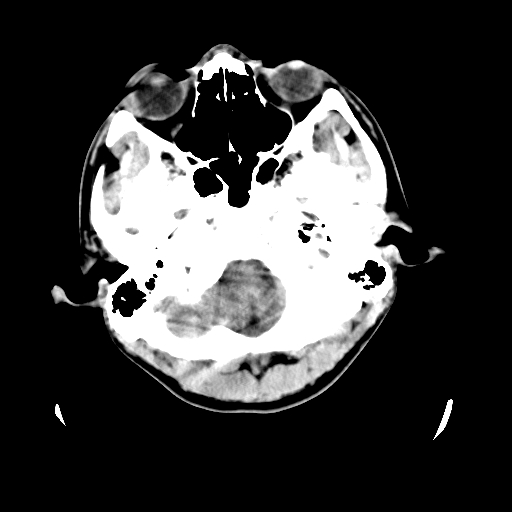

标题: CT23601:男, 17岁,剧烈头痛一小时。 [打印本页]

男, 17岁,剧烈头痛一小时。

颅脑ct轴位平扫颅内未见明确异常;建议:必要时复查。

颅脑ct平扫颅内未见明确异常;剧烈头痛,建议必要时dsa造影。